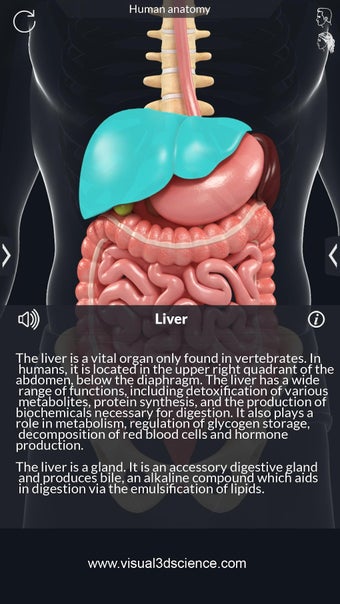

La anatomía humana es una aplicación educativa médica que te permite explorar el cuerpo humano desde todos los ángulos. Ofrece una mirada detallada a la anatomía de los diferentes sistemas, así como a los órganos y sus funciones. Es una referencia perfecta para estudiantes y profesores de medicina.

Puedes seleccionar cada parte del cuerpo por separado para ver su nombre o leer información relacionada. Puedes ocultar y mostrar cada parte del cuerpo, así como rotar 360° alrededor de un modelo 3D altamente realista. Puedes dibujar en la pantalla o compartir capturas de pantalla con tus amigos. Puedes encontrar la definición de cada parte del cuerpo y su anatomía.